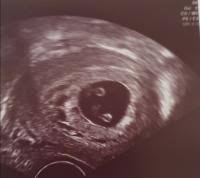

In dieser Fruchthöhle finden sich gelegentlich bereits kleine weißliche Flecken die durch die embryonalen Strukturen hervorgerufen werden. Woche SSW5 Alter 3 Wochen. In der Regel werden Zwillinge bereits bei der ersten Ultraschalluntersuchung entdeckt die etwa in der sechsten Schwangerschaftswoche erfolgt.

Grösse 15-3 mm - so gross wie ein Sesamkorn. Schwangerschaften entstehen - und das ist nun wirklich nicht überraschend neu - nachdem eine Eizelle von einem Samenfaden befruchtet wurde.